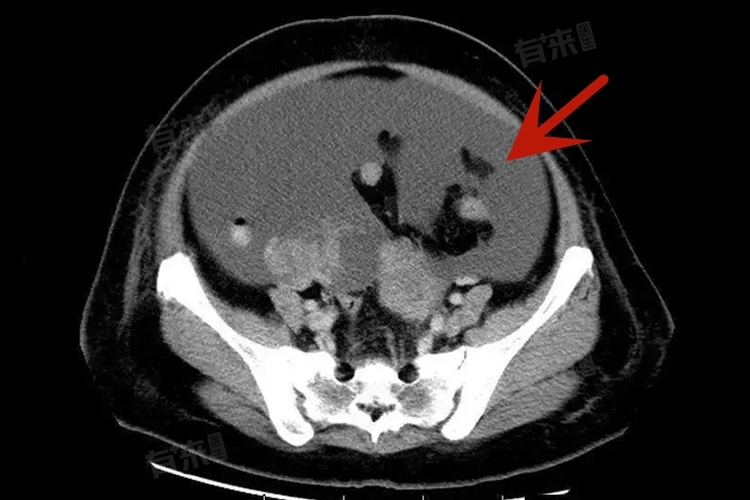

- 黏液性囊腺瘤通常体积较大,有时可充满整个腹腔。对于良性的黏液性囊腺瘤,手术完整切除是主要治疗手段,包括切除患侧附件。若能将肿瘤完整剥离,不出现破裂,根治效果较好。然而,一旦肿瘤破裂,囊内黏液种植在腹腔,可能引发腹腔黏液瘤,导致病情反复,增加根治难度,影响治疗效果。